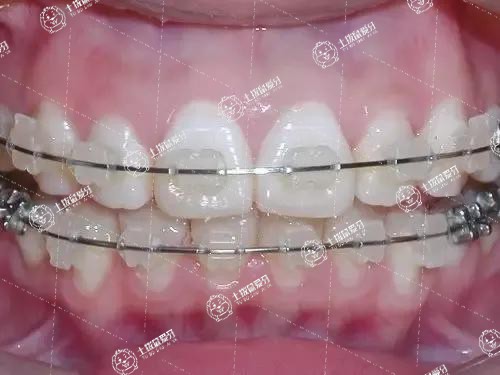

牙齒深覆合矯正的方法需要根據(jù)引起深覆合的原因具體選擇,一般來(lái)說有佩戴固定矯治器和正畸治療和正頜手術(shù)聯(lián)合治療等方式。

矯正牙齒深覆合前需要先進(jìn)行詳細(xì)的檢查,以及拍攝X光牙片來(lái)確定引起深覆合的原因。如果是牙源性的深覆合,則采取佩戴固定矯治器的方式進(jìn)行正畸治療,矯正深覆合,一般來(lái)說在12歲左右進(jìn)行治療。

矯正牙墊高主要是針對(duì)患者的前牙深覆合、前牙反頜、后牙鎖頜等情況而進(jìn)行的矯正方案,具有保護(hù)牙齒、調(diào)整牙齒的咬合關(guān)系的作用。矯正牙齒初期,牙齒墊高后牙齒咬合會(huì)受影響,不方便吃東西,因此患者可以通過調(diào)整進(jìn)食方式、食物選擇、飯后護(hù)理等方面進(jìn)行緩解。